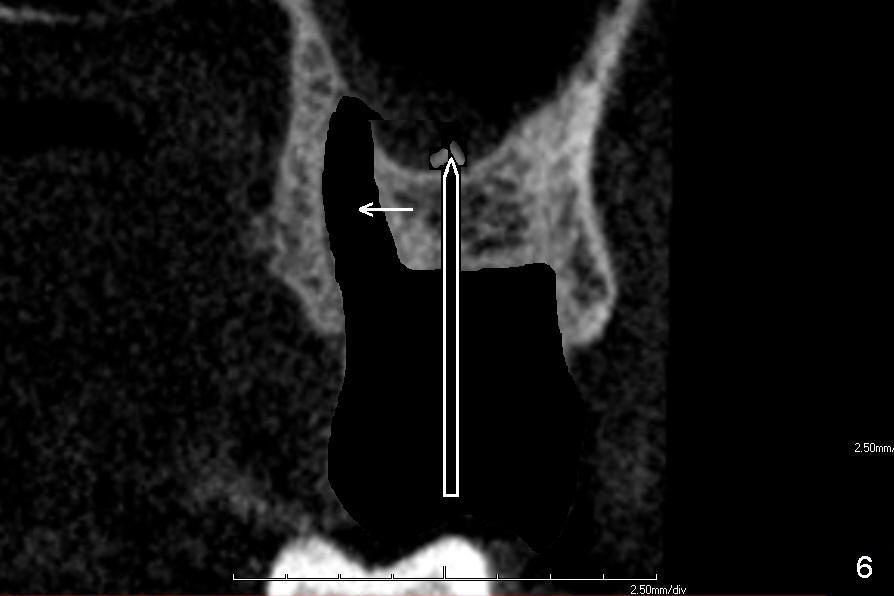

If the septum is not so bad in size, osteotomes (RT series) will be used to expand it (to obliterate 3 sockets) and finish sinus lift to increase implant length if bone is not too hard to manipulate (Fig.6,7). Osteotomy is finished by using proper size and length of taps. Finally a large, but relatively short implant is placed in the septum (Fig.8). Arrowheads in Fig.6-8 indicate that as osteotomes are driven in sequentially (Fig.6,7 white box) and the implant is placed (Fig.8), bone segment may be moved palatally to obliterate the palatal socket gradually.